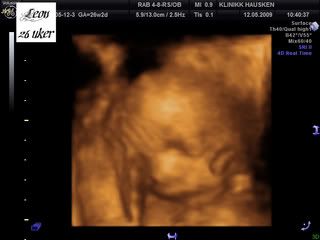

Så, her er bildene av gutten vår:

Han ble målt til å være nesten 1100 gram allerede nå! Det betyr at han er 14 % over gjennomsnittet! Så legen på Hausken ville ha meg til glukosebelastningstest for å utelukke svangerskapsdiabetes[&:] Jeg er egentlig i høy risk for det, i og med at jeg har PCOS, var noe overvektig før graviditet, og jeg har diabetes type 2 i familien.